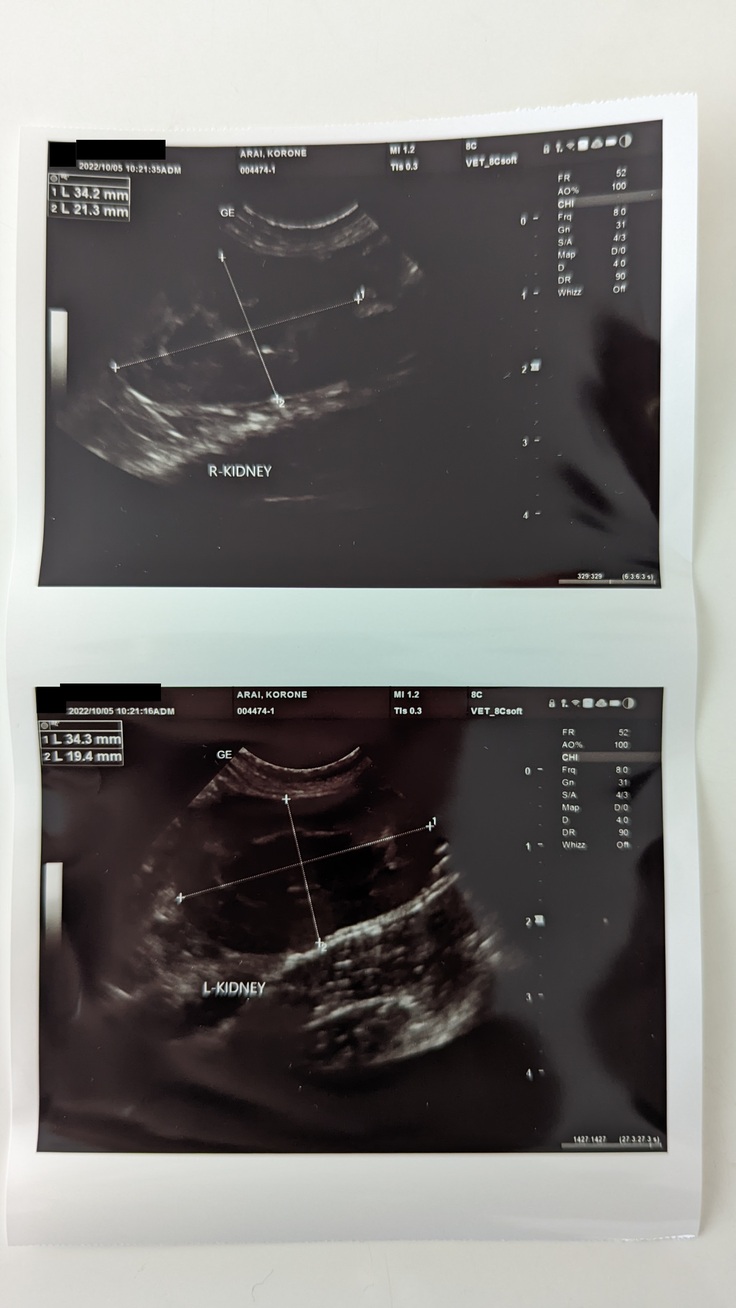

エコー写真も撮りましたが腹水も全くない状態でした!

※各動物病院様に掲載許諾を頂いておりますが、病院のご希望で、病院名はマスクさせて頂いております。